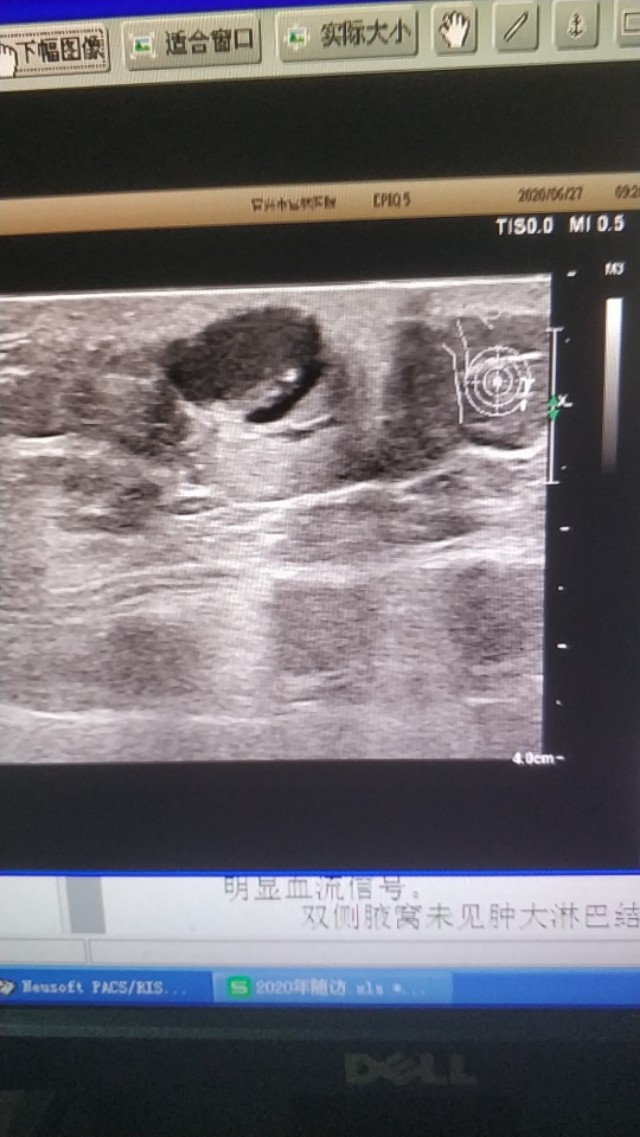

上图是一个左膝部的表皮囊肿,与皮肤真皮层关系密切,里面回声细密伴裂隙样低回声。